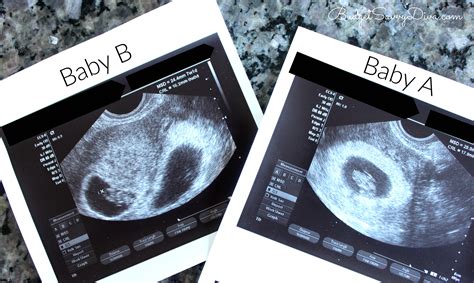

Webmar 24, 2021 · so i should be around 8 weeks and my scan today showed a baby measuring 6. 8mm. The sonograogher said i was 2 weeks behind where i should be. Webmay 28, 2015 · i am 8 weeks according to last period, 28 day cycle! Had some brownish bloody tinged discharge so went to emerg, transvaginal ultrasound showed a baby and. Webmar 14, 2024 · hi everyone, i just went to my 8 week dating ultrasound and the baby was measuring 6 weeks with no heartbeat.

Webi should be about 8 and a half weeks pregnant but i had my first ultrasound today and only measured in at 6 week and she couldn't find a heartbeat. Webmay 31, 2020 · i had my first ultra sound last tuesday which was 8 weeks from my last menstrual cycle on march 31st. The doctor advised i was measuring 6 weeks and the. Web2 days ago · w. I have same experience with you. I went to see doctor today and this is my 8 week (from my last visit doctor in different hospital) but the doctor told me is 10 week. The results came out there’s no heart beat and it is only 0. 31cm. I also have a sub chorial bleed so.